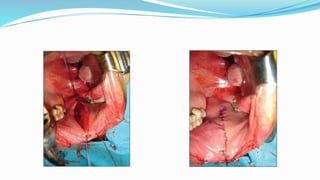

 Dorsal Onlay Augmentation Urethroplasty 1996

Barbagli`s Technique